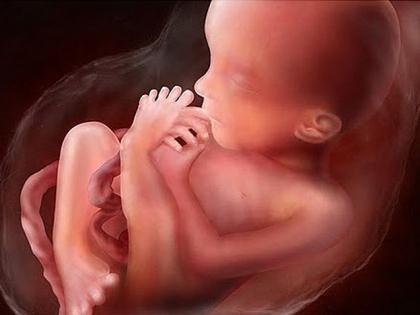

Малыш на 18 неделе беременности

К концу 18 недели масса плода составляет – 150 г, длина тела – 13 см. Начиная с этого срока, вес и рост ребенка будет увеличиваться быстрее, что связано с интенсивным развитием костной, мышечной ткани и подкожной жировой клетчатки.

В организме плода на 18 неделе жизни происходит целый ряд серьезных событий:

- Подходит к концу формирование иммунной системы, появляется тимус (вилочковая железа) – орган, отвечающий за продукцию и иммунологическое «обучение» Т-лимфоцитов.

- Начинает функционировать эпифиз – железа внутренней секреции, выделяющая в кровь биологически активные вещества, которые обуславливают появление и синхронизацию биоритмов сна и бодрствования.

- Молочные зубы, находящиеся пока еще в челюстях, покрываются дентином, рядом с ними происходит закладка постоянных зубов.

- Укрепляется за счет отложения кальция костная ткань.

- У девочек заканчивается формирование внутренних половых органов. Если будущая мама пойдет на УЗИ, на этой неделе врачу уже не составит труда определить половую принадлежность малыша, поскольку процесс образования наружных гонад также уже завершился и у мальчиков, и у девочек.

- Продолжается совершенствование органов чувств. Малыш уже хорошо слышит, может различать яркий свет, усиливается кожная чувствительность.

На 18-й неделе беременности врачи отмечают значительные изменения как у матери, так и у плода. Малыш продолжает активно расти: его длина достигает около 14-15 см, а вес составляет примерно 200 граммов. В этот период формируются основные органы и системы, а также начинается развитие чувств. Плод может реагировать на звуки и прикосновения, что свидетельствует о его растущей нервной системе.

В этот период активно продолжаются рост и развитие плода. Развиваются системы регуляции и эндокринная система, нарастает масса тела плода, структуры коры головного мозга будущего ребёнка усложняются. Все оболочки плода уплотняются, но через них продолжают просвечивать кровеносные сосуды.